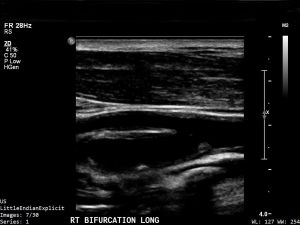

After ophthalmologic evaluation, laboratory tests include inflammatory markers like erythrocytes sedimentation rate (ESR) and C-reactive protein (CRP) to evaluate for GCA in elderly patients. Imaging of the carotid arteries and cardiac evaluation are generally recommended. Neuroimaging (e.g., magnetic resonance imaging (MRI) of the brain) and vascular imaging (e.g., CTA or MRA of head and neck) may show intracranial vascular occlusive disease, brain ischemia, or prior stroke. Electroencephalogram (EEG) may be indicated if the TVL was bilateral or if the history suggests a seizure.[6] Transthoracic echocardiography (TTE) and transesophageal echocardiography (TEE) are essential for identifying cardiac myxoma, and should be considered when accompanied symptoms suggest of cardiogenic source or in patient without clear predisposing vascular risk factor and unable to identify source of emboli. [5]